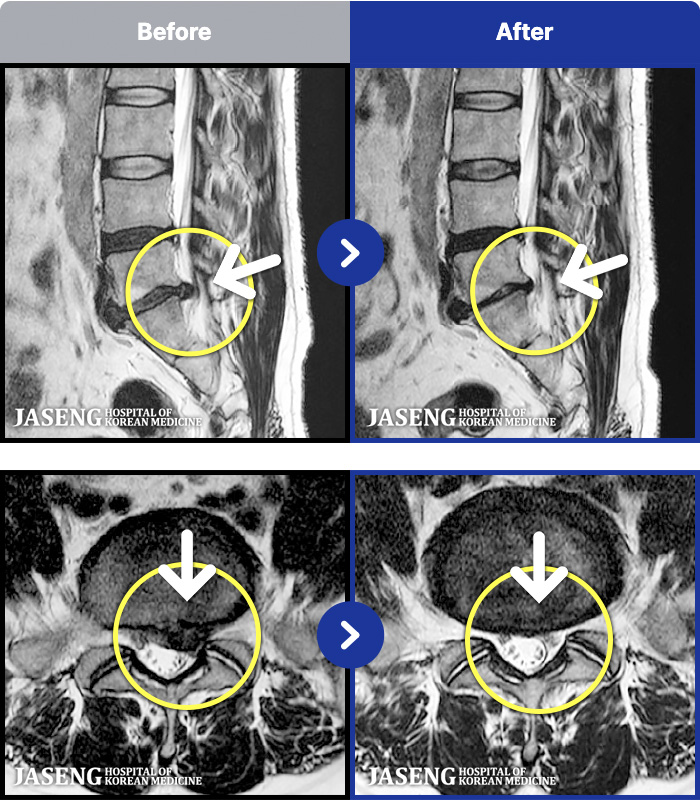

1,296 MRI ũ ʸ Ȯϼ.

[] 23.11.11~25.06.04